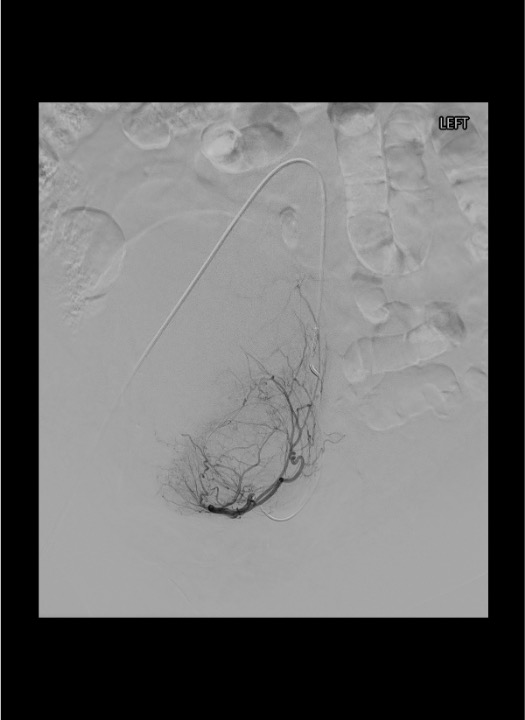

Embolization — Left Uterine Artery

Angiographic Landmarks

Uterine Artery Identification

- IIA angiogram: uterine artery courses medially from the anterior division toward the midline pelvis

- Characteristic “hook” or “U-turn” as it crosses over the ureter and turns superiorly along the lateral uterus

- Fibroids demonstrate a dense vascular blush on arterial phase — confirms fibroid vascularity and supply from this uterine artery

Critical Branch Points

- Cervicovaginal branch takeoff: arises from the uterine artery early in its course; supplies cervix and upper vagina; must embolize DISTAL to this branch

- Ovarian artery collateral supply: look for retrograde filling of ovarian artery at the fundus on late-phase images; if prominent, consider aortogram to evaluate for accessory ovarian artery supply requiring separate embolization

- Anastomotic arcade: ascending uterine artery connects with descending ovarian artery at the fundus — this is the route for potential non-target ovarian embolization